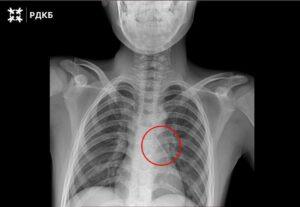

11-летний мальчик из Калининграда был экстренно доставлен в Москву после того, как вдохнул булавку. Хирурги успешно провели...

11-летний мальчик из Калининграда был экстренно доставлен в Москву, где врачи успешно извлекли булавку из его дыхательных...